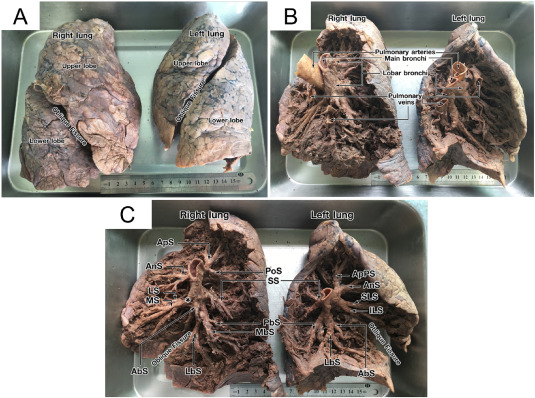

1. Severe lung damage - a life without breath

Over time, chronic inflammation and toxin buildup cause irreversible damage to the airways and lung tissue.

The lungs lose their ability to absorb oxygen efficiently. No quick remedy can restore what's been destroyed.

2. COPD progression - the silent suffocator

Untreated lung congestion and airway inflammation often develop into full-scale COPD.

It may begin with mild shortness of breath or an occasional cough-but the damage continues silently.

Before patients realize what's happening, their lung capacity has already declined significantly.

Breathing feels like trying to inhale through a straw.

Most are diagnosed too late-when the condition can only be managed, not reversed.